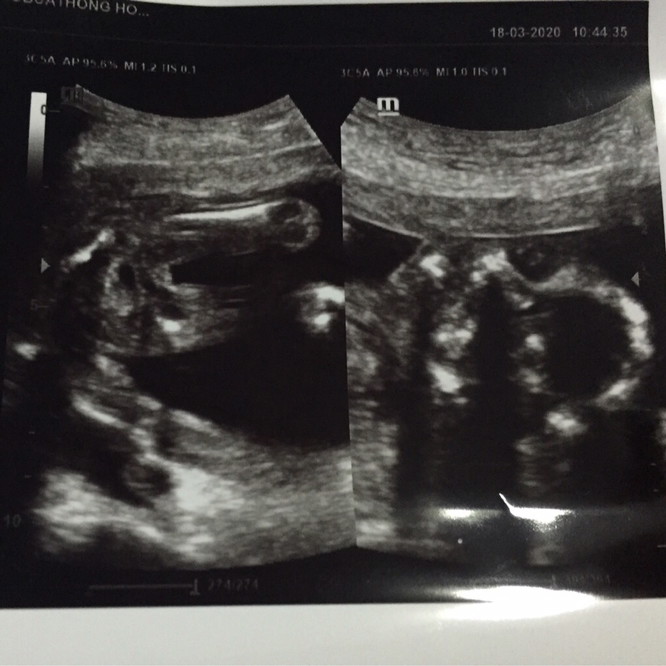

หมอบอกไม่ฟันธงหรอก ชายหรือหญิง แต่ที่ชัวร์ๆคือชาย90กว่า% 555555 แม่ๆว่าไงคะ ปล.คุณพ่ออยากได้ลูกสาว #เพื่อความบันเทิงนะคะ ไม่เอาดราม่าคะ^^

น่าจะชายค่ะ แต่ระวังเป็นสายสะดือนะคะ คุณหมอบอกว่าบางคนดูผิดค่ะ

อาจจะผญก็ได้คะ ที่โผล่ออกมาอาจเป็นมือ ทำใจกลางๆไว้คะ

น่าจะชายค่ะเพราบ้านนี้ก็จับได้ท่านี้เหมือนกัน